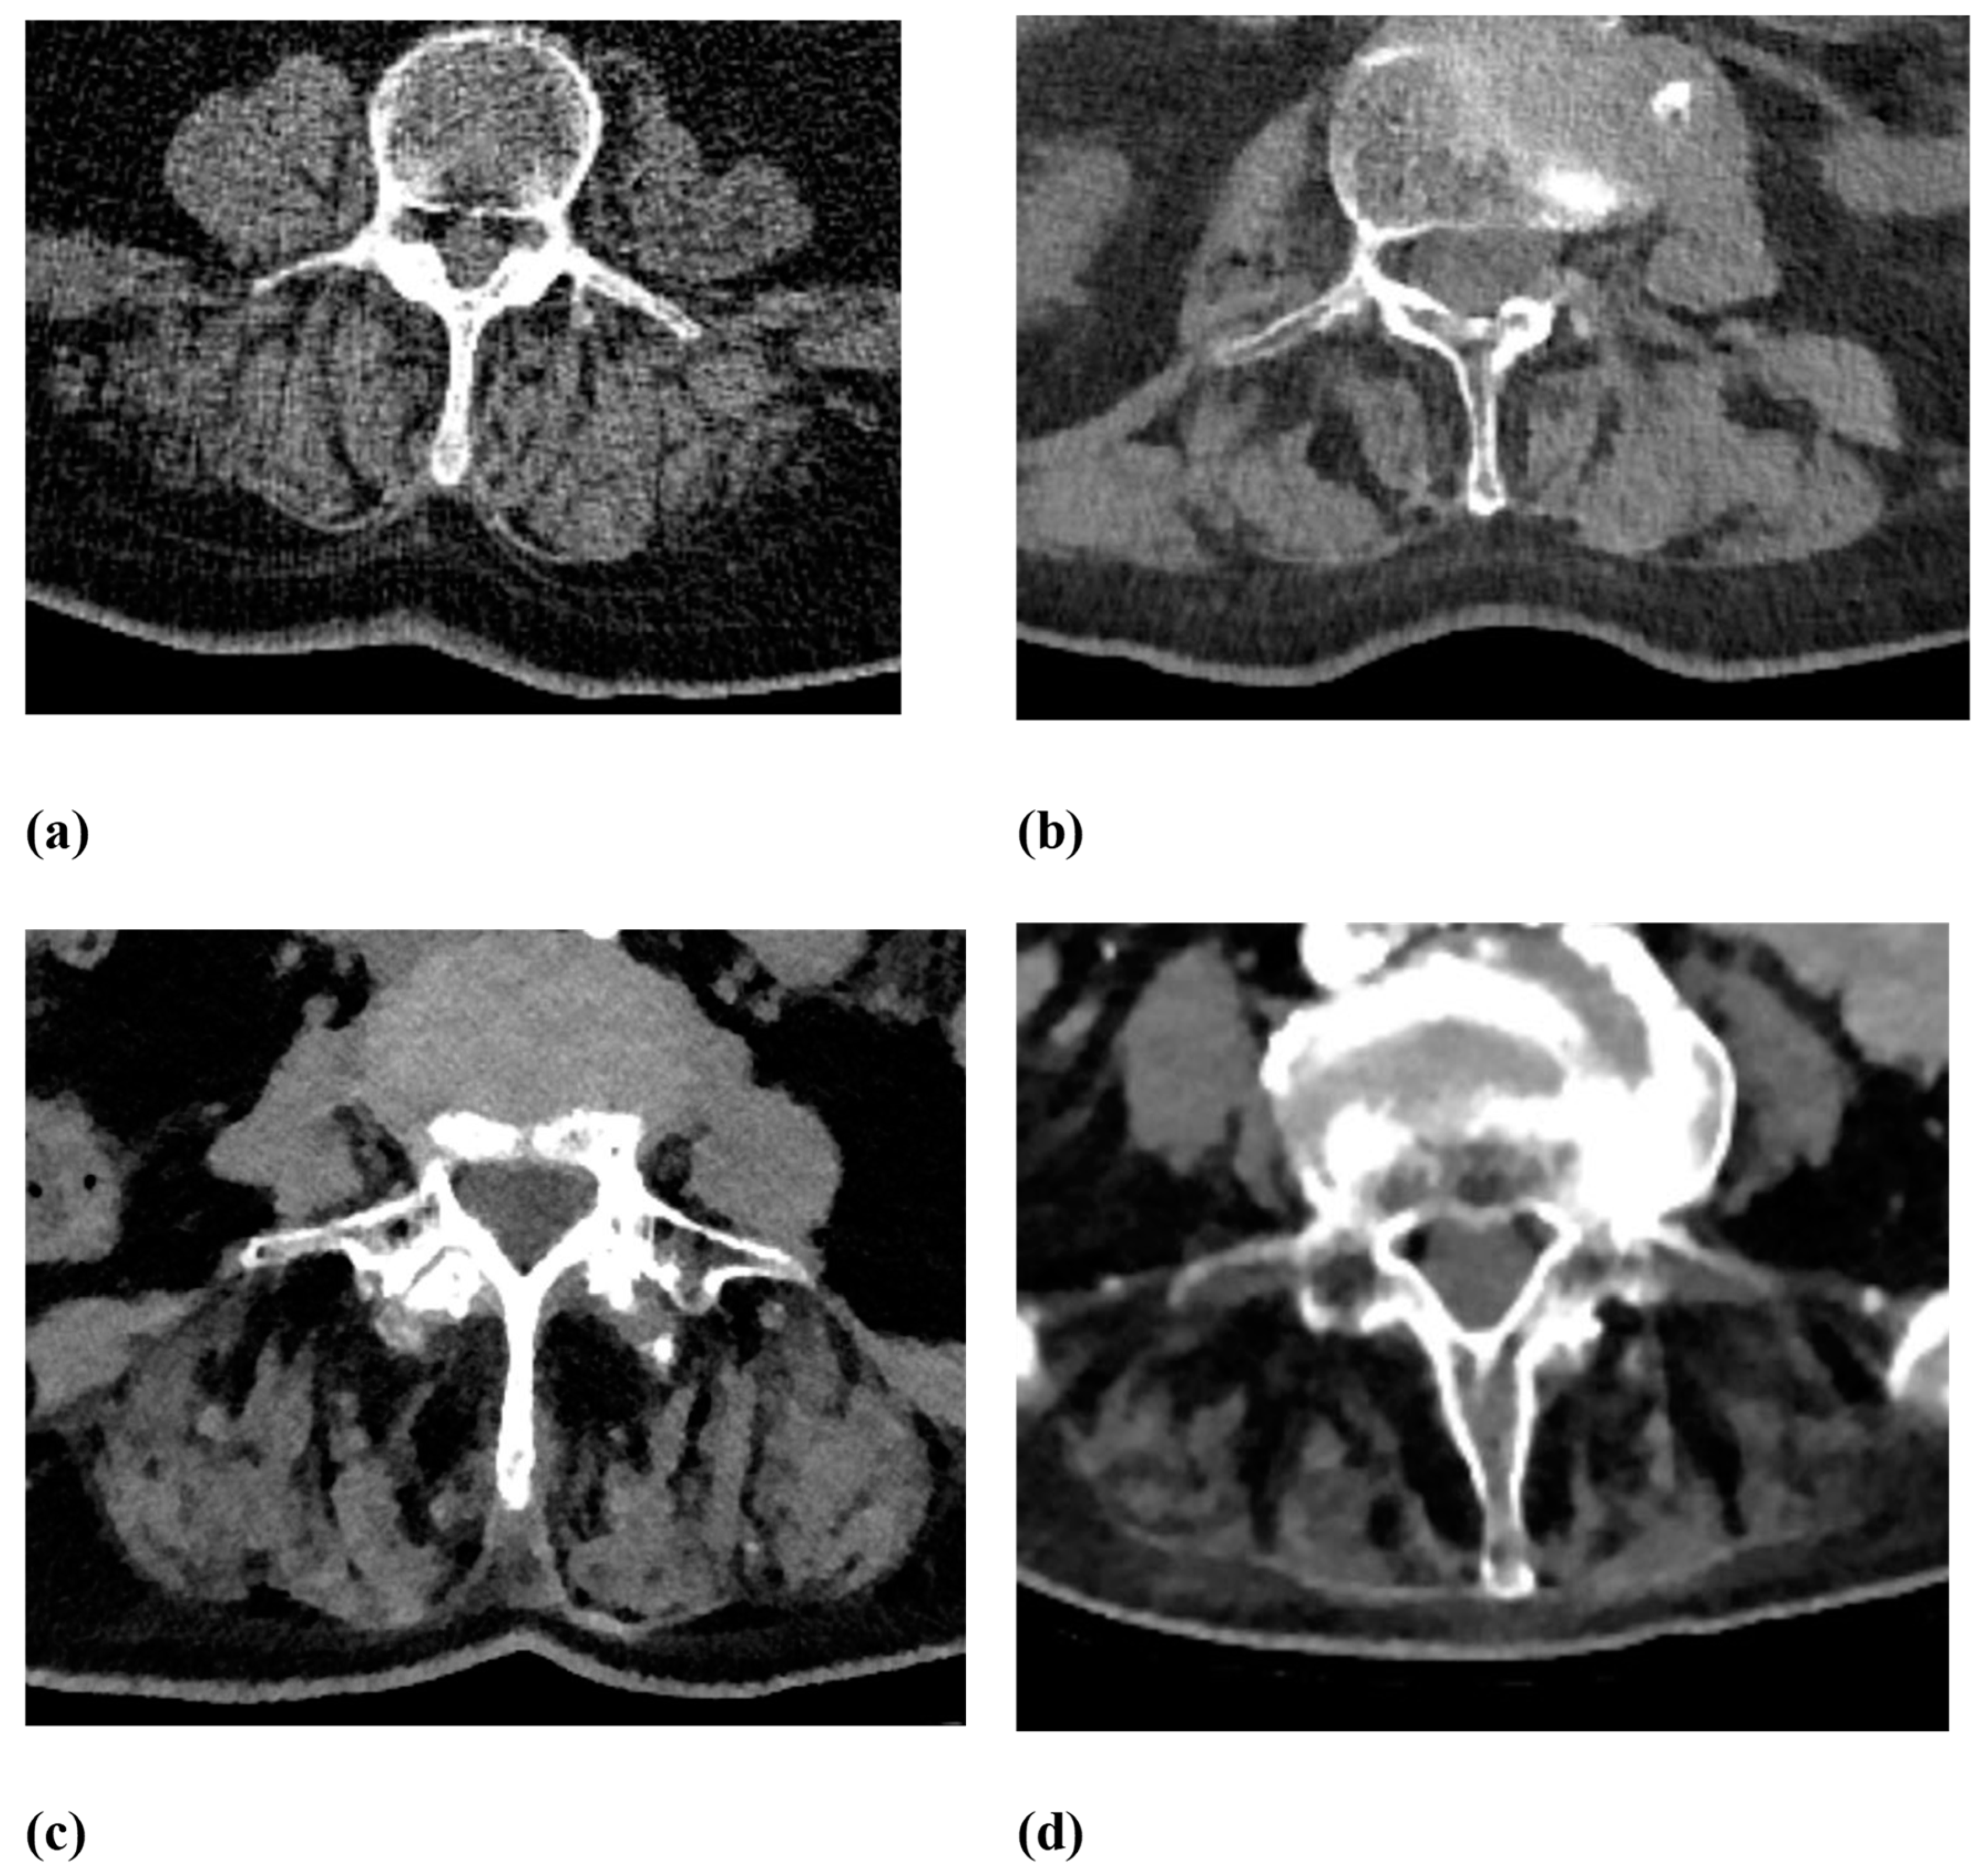

2.2. Image Analysis

| Fatty degeneration of the autochthonous back muscles | Goutallier score 0–4:

|